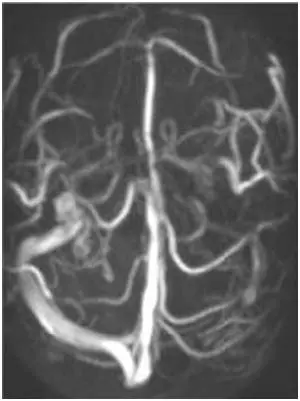

Obiettivi: L’emicrania cronica (CM) è caratterizzata da dolore ricorrente alla testa, spesso associato ad alterazioni elettroencefalografiche (EEG) e ad asimmetrie nella circolazione venosa intracranica. È considerata uno dei sintomi della insufficienza venosa cerebrospinale cronica (CCSVI).

Metodi: Sette pazienti con diagnosi di CCSVI ed emicrania cronica, con o senza altri sintomi, sono stati sottoposti a angioplastica transluminale percutanea (PTA) delle vene giugulari interne. Tutti hanno eseguito risonanza magnetica venografica e/o ecocolordoppler prima della PTA, sette EEG preoperatori e cinque EEG di controllo post-PTA. L’intensità del dolore è stata valutata con una scala numerica prima e dopo l’intervento.

Risultati: Tutti i pazienti hanno mostrato un miglioramento del flusso ematico giugulare dopo PTA. In cinque pazienti su sette è stato osservato un miglioramento del ritmo alfa cerebrale all’EEG post-operatorio e tutti hanno riportato una significativa riduzione del dolore.

Conclusioni: Queste osservazioni preliminari suggeriscono una stretta associazione tra emicrania cronica, anomalie venose intra- ed extracraniche e alterazioni EEG, e indicano la venoplastica come possibile approccio terapeutico da approfondire.